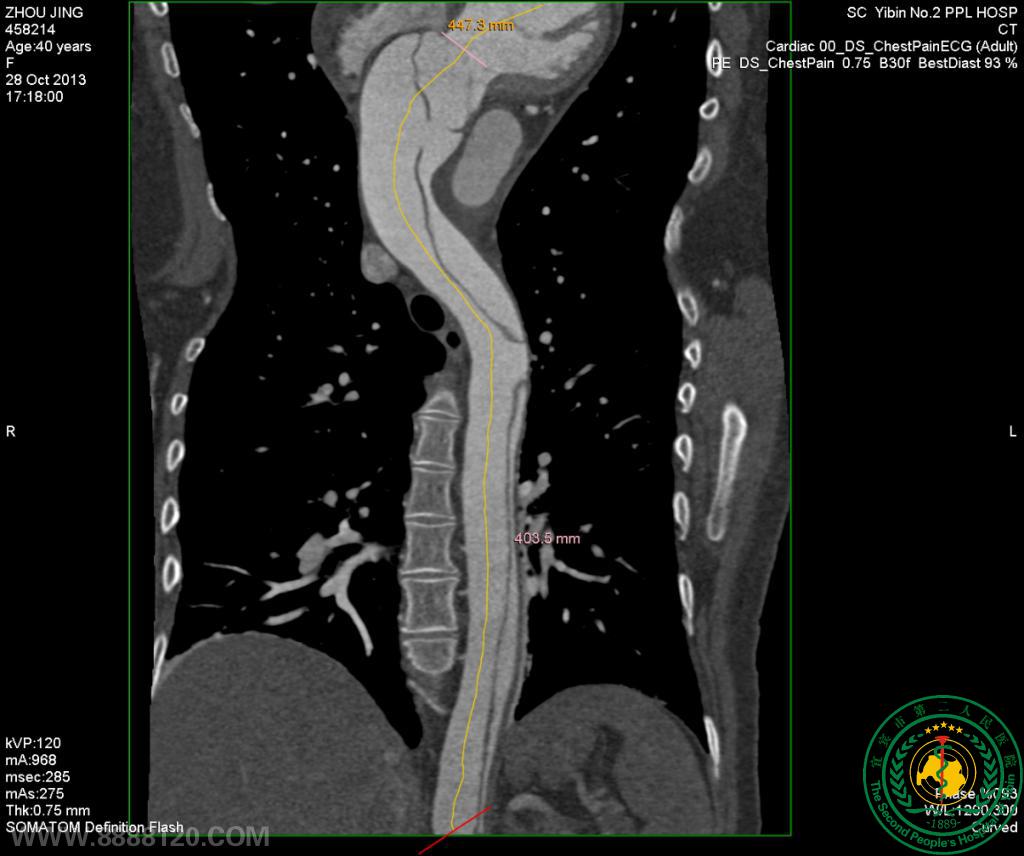

我院CT室推出胸部血管(冠状动脉、肺动静脉、主动脉)一站式检查技术

我院CT室推出胸部血管(冠状动脉、肺动静脉、主动脉)一站式检查技术5607